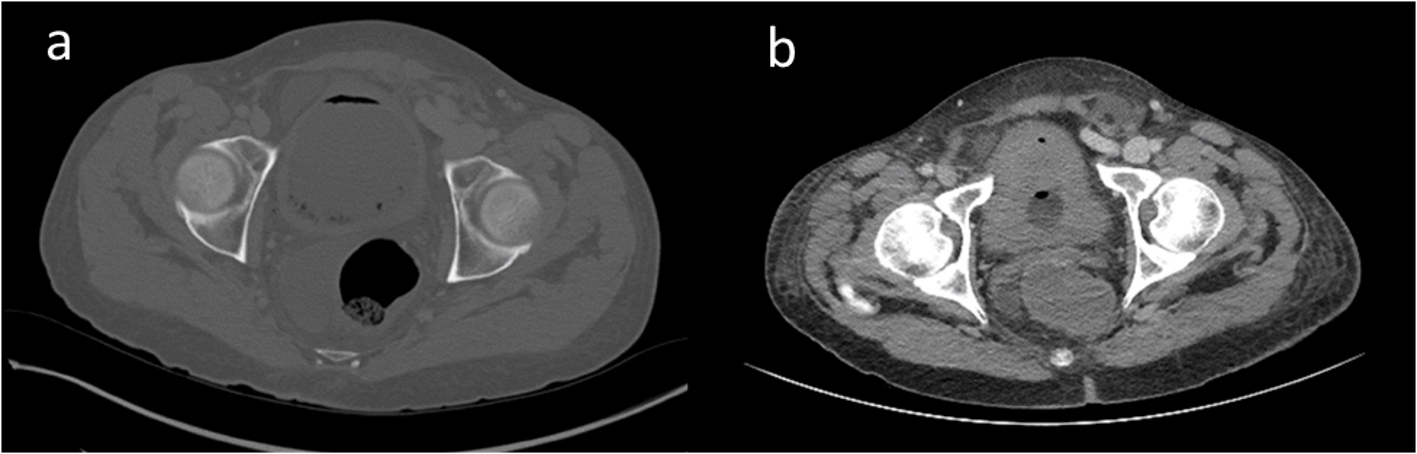

On admission, vital signs showed fever (temperature 38.7 °C), tachycardia (pulse rate 135 beats/min), and tachypnea (respiratory rate 28/min). His blood pressure was 132/69 mm Hg. Physical examination revealed mild icterus sclera, abdominal distension and abdominal tenderness, particularly in the peri-umbilical region. Laboratory testing revealed white blood cell (WBC) count of 2.8 × 109/L, hemoglobin of 10.4 g/dL, platelet count of 59 × 109/L, and lactate level of 3.6 mmol/L. Urine analysis disclosed leukouria, bacteruria and 11 - 30 red blood cells per field. Because of the abdominal findings, a CT scan of the abdomen and pelvic was performed, which demonstrated multiple non-dependent gas foci within the thickened bladder wall, suggestive of emphysematous cystitis (Fig. 1a).

![]() Click for large image | Figure 1. Computed tomography at admission showed multiple non-dependent gas foci within the thickened bladder wall suggestive of emphysematous cystitis (a) which was markedly improved following catheter decompression and antibiotic therapy (b). |

Blood and urine cultures confirmed Klebsilla pneumonia as the causative agent. Antibiotic therapy started with piperacillin-tazobactam in addition to fluid resuscitation and bladder decompression with catheter reinsertion. At 7 days, a follow-up CT scan delineated a markedly improved appearance of emphysematous cystitis following catheter decompression (Fig. 1b). Antibiotic was transitioned to ceftriaxone, and indwelling catheter was removed. A high-grade fever, however, developed, which was ultimately attributed to possible beta-lactam drug reaction following negative repeated infectious work-up. Within 24 h of starting levofloxacin, fevers resolved. Finally, the patient was discharged to home with oral levofloxacin regimen to complete a 14-day course.

Laboratory testing demonstrates positive urine cultures with E. coli or Klebsiella pneumoniae in 80% of the cases of emphysematous cystitis [4], just as we found in our patient. Imaging, particularly CT scan, has a key role in the diagnosis and assessment of the disease, characterized by multiple non-dependent gas foci within the thickened bladder wall, as observed in our case [5]. Bladder catheterization for optimal drainage and irritation with antibiotic therapy and blood glucose control are recommended treatment for emphysematous cystitis, resolving the infection in majority of cases as observed in this patient. Emphysematous cystitis is a life-threatening disease and may result in urosepsis and even death in up to 7% of the cases [2, 3].